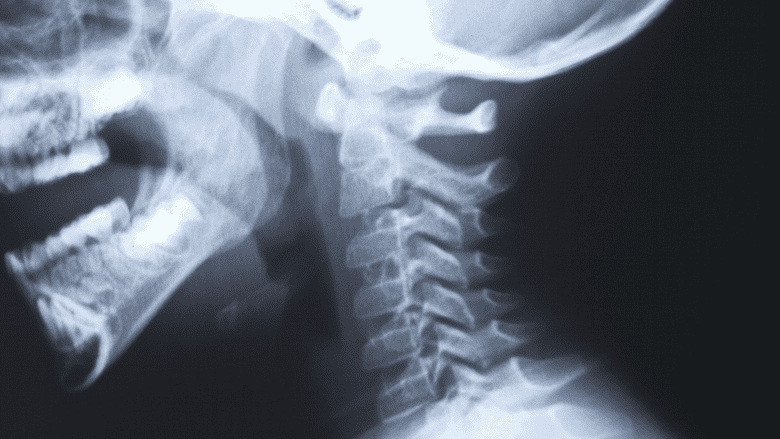

Diagnostic imagery such as x-rays, computerized tomography (CT) scans, and magnetic resonance imaging (MRI) may only be used to support a diagnosis, but do not generally confirm the diagnosis in CGH. Cervical disc bulging as seen in these images may not always indicate the cause of CGH. This technique is more useful to identify causes such as tumors or birth defects.